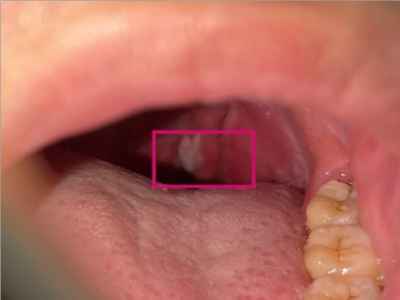

化脓性扁桃体炎单侧扁桃体上有两个黄白色异物图

化脓性扁桃体炎一侧的扁桃体上有黄白色物质,大小不等,形状不规则,镶嵌在增生肿大的扁桃体黏膜上,还可能伴有发热、恶寒、四肢疼痛等症状。